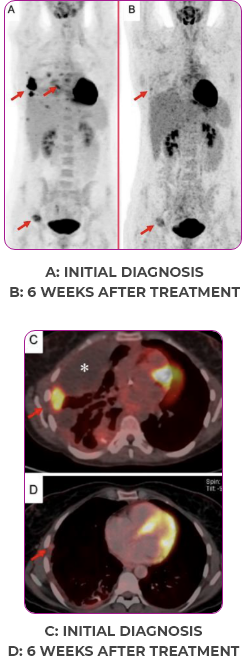

Response in primary and metastatic lesions1

MRIa imagery of the lungs. Arrow indicates large target lesion in left lung.1

SCAN 1: LUNG

MRIa imagery of the brain. Arrow indicates large target lesion in left lung.1

aMRI, magnetic resonance imaging.

Images courtesy of Dr Fabian Pitoia.

Response to VITRAKVI1

- After 8 weeks on VITRAKVI, all target lesions had disappeared, demonstrating a complete response

- The complete response was sustained over 11 months of treatment with VITRAKVI

- Patient experienced Grade 1 fatigue and mild hepatic enzyme elevation